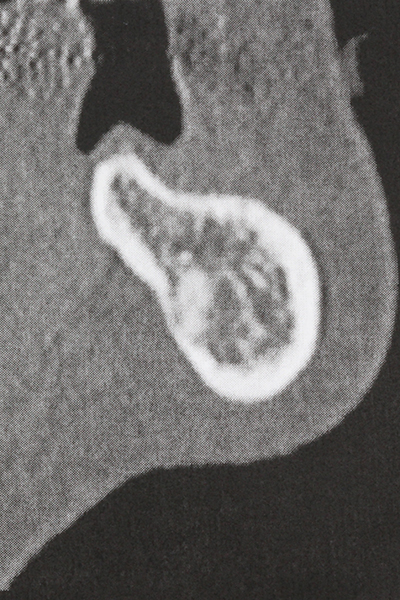

Aplicación: Preparación cerca del nervio

Como ya se ha mencionado, en el ámbito de la odontología conservadora también existen áreas en las que está indicada la cirugía piezoeléctrica. El uso de insertos de trabajo especiales facilita la representación del ápice radicular y, sobre todo en el área de los premolares inferiores y superiores, protege mejor los nervios y las mucosas del seno maxilar. En el caso de un cierre apical no estanco, los insertos de diamante acodados preparan de forma exacta y selectiva la cavidad de resección para el material de relleno retrógrado de la raíz. Gracias a la técnica de ultrasonidos, los insertos pueden presentar un diseño muy estilizado, lo que mejora la visión global y el tamaño de la cavidad de acceso. De este modo, en esta indicación, el uso de la cirugía por ultrasonidos se encuentra entre los métodos estándar para una apicectomía (Del Fabbro, Tsesis et al. 2010, Scarano, Artese et al. 2012).

Si es preciso realizar intervenciones quirúrgicas en las que el hueso está en contacto directo con estructuras sensibles, como son los vasos sanguíneos o los nervios, los instrumentos rotativos presentan un enorme potencial de provocar lesiones iatrogénicas. Así, precisamente en la representación de nervios después de una lesión iatrogénica, o en el transcurso de la lateralización de un nervio para resecciones, reconstrucciones o incorporación de implantes, los equipos piezoeléctricos pueden resultar muy útiles para preparar la tapa ósea y retirar las partes de tejido duro cercanas al nervio (fig. 17-20). Por lo general, un ligero contacto del cordón nervioso con el inserto piezoeléctrico no tiene consecuencia alguna; ahora bien, un procedimiento poco cuidadoso con movimientos tipo sierra o piezas de trabajo sobre la base ósea aún existente puede provocar lesiones nerviosas temporales o incluso permanentes. Con todo, el riesgo de sufrir una lesión de este tipo se considera significativamente inferior que en los casos en los que se utilizan sierras y fresas (Pereira, Gealh et al. 2014).